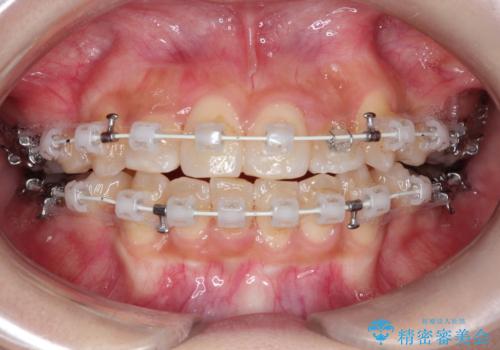

重度の歯並びの乱れを改善|上下4本抜歯と審美ワイヤー矯正で美しい歯列へ

- 患者様は、歯並びのガタガタ(重度の叢生)を改善したいとのことで来院されました。診察すると、歯列のスペース不足が著しく、前歯が重なり合い、噛み合わせにも影響が出ている状態でした。歯をきれいに並べるためには抜歯によるスペース確保が不可欠と判断し、上下の小臼歯4本を抜歯したうえで、目立ちにくい審美ワイヤー矯正(白いワイヤーと透明ブラケット)を用いた治療計画を立てました。

抜歯によって歯を動かすためのスペースを確保。その後、審美ワイヤー矯正を用いて歯を1本ずつ適切な位置に誘導しながら、噛み合わせのバランスも整えていきました。時間はかかりましたが、ガタガタの歯並びがきれいに整い、機能的にも審美的にも満足のいく仕上がりとなりました。患者様からは「歯並びが劇的に改善し、見た目だけでなく噛みやすさも向上した」と喜びの声をいただきました。